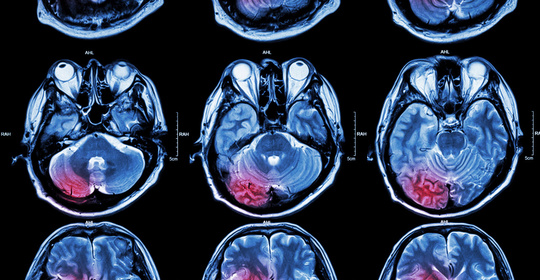

腦實質出血:應對急救和康復的實用指南!